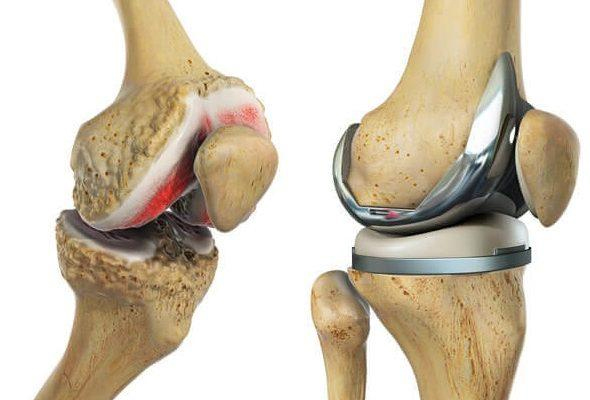

His areas of expertise include fracture and trauma care, providing prompt and effective treatment for bone and joint injuries. Dr. Siddiqui specializes in joint replacement surgeries, including Total Knee Replacement and Total Hip Replacement, helping patients regain mobility and live pain-free lives. He also treats sports and ligament injuries with advanced arthroscopic procedures for faster recovery and minimal discomfort.

Advanced joint replacement surgery restores mobility, reduces pain, improves quality of life, ensures full recovery.